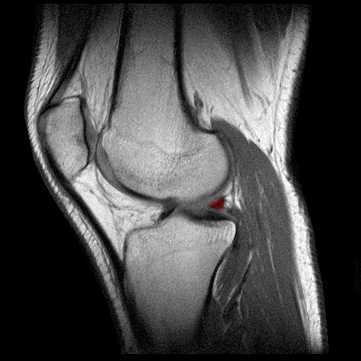

MENISCO INTERNO: CUERNO POSTERIOR

El menisco interno ayuda a estabilizar el cóndilo lateral femoral y hace de cojin en superficie articular. Tiene una forma casi anular: por su extermo anterior se origina en la proximidad de la espina de la tibia, inmediatamente por delante de la tuberosidad externa de la misma. Su parte posterior se fija entre la vertiente posterior de la espina tibial, en la tuberosidad externa de esta.